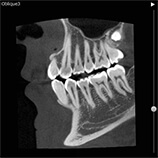

当クリニックでは歯科用CT装置を導入しています。

歯科用の3次元CTにより、いままで以上に詳細な診断ができるようになりました。

インプラント、歯周病、根管治療(歯の根の治療)、顎関節症などの治療時に有効です。

※CT画像一例